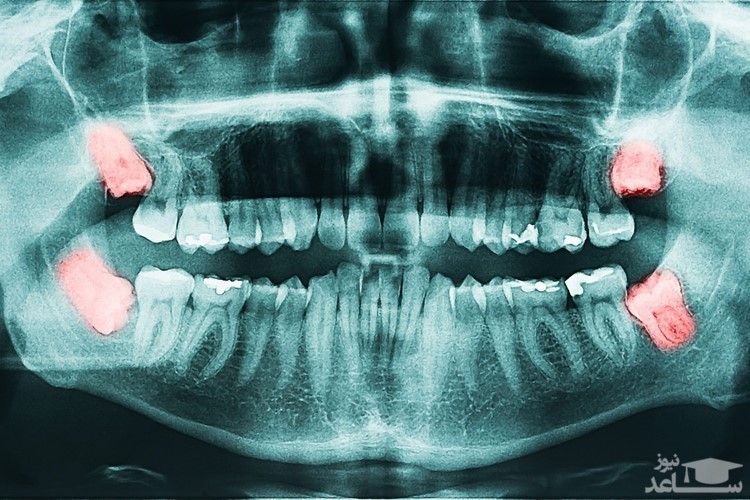

دندان عقل یا دندان مولار سوم یکی از سه دندان مولار در هر ربع از دندان های انسان است. دندان عقل عقب ترین دندان از مجموعه دندان های آسیاب بزرگ است. اکثر بزرگ سالان دارای چهار دندان عقل هستند ( یکی در هر ربع دندانی)، اما ممکن است تعداد دندان های عقل هیچ، کمتر یا بیشتر باشد. در اغلب افراد معمولاً «دندان های عقل»، در اواخر نوجوانی یا اوایل دهه ۲۰ سالگی ( حدود سن ۱۷ تا ۲۵ سالگی ) شروع به درآمدن می کنند. هرچند برخی از افراد ۱۲-۱۴ ساله نیز ممکن است دندان های عقلشان زودتر درآیند. در اغلب موارد رشد این دندان ها با مشکلاتی همراه است.

دندان عقل ، یا دقیق تر بگوییم دندان های عقل، شامل ۴ دندان میباشد.۲ دندان عقل در فک بالا و ۲ دندان عقل در فک پایین که در ۴ گوشه دهان قرار دارند. به عبارت دیگر آخرین دندان در هر قوس فکی- به شرط حضور همه دندانها- را دندان عقل گویند. عموما رویش این دندان ها در سنین ۱۷ تا ۲۵ سالگی است. دندانپزشکان اصطلاحا آن را آسیای سوم می نامند. گاهی برخی عوامل مانند ارث، بیماری های دوران کودکی(کم خونی، راشیتیسم )، عدم هماهنگی رشد استخوان فک با اندازه دندان ها و … منجر به نهفته ماندن این دندان ها در داخل فک می شوند. یا این احتمال وجود دارد که به طور ناقص رشد کنند طوری که تنها بخشی از تاج دندان قابل مشاهده باشد که در این حالت به آن دندان عقل نیمه نهفته گفته می شود. متخصصان دندانپزشکی آمریکایی معتقدند که دندان عقل را تنها زمانی که منجر به بروز مشکل و ناراحتی شود، باید کشید زیرا نگه داشتن ان در این صورت عاقلانه نیست.

بسیاری از افراد که از بهم ریختگی دندان های خود شاکی و ناراحت هستند، رویش دندان عقل و فشار آن بر دیگر دندان ها را مقصر می دانند و به همین دلیل اصرار دارند تا هر چه سریع تر دندان های عقل را از دهان خود خارج کنند. این در حالی است که شرایطی برای خارج کردن دندان عقل نهفته یا نیمه نهفته از دهان لازم است که بر اساس آن ها بسیاری از دندان پزشکان به بیمارانشان توصیه می کنند تا دندان عقل را بکشند. انجمن دندانپزشکی آمریکا در جدیدترین مقاله ای که منتشر کرده است، بیان می کند: اگر دندان عقل شما عامل بروز مشکلات دهان و دندان است، حتما باید برای کشیدن آن به موقع به دندانپزشک مراجعه کنید. اما جالب است بدانید که تحقیقات جدید حاکی از آن است که تاثیر رویش دندان عقل در به هم ریختگى دندان های فک بسیار ناچیز و تقریبا در حدود ده درصد است. پس برای کشیدن دندان عقل عجله نکنید، باید علت به هم ریختگی دندان ها را بیابید و سپس برای رفع آن اقدام کنید.